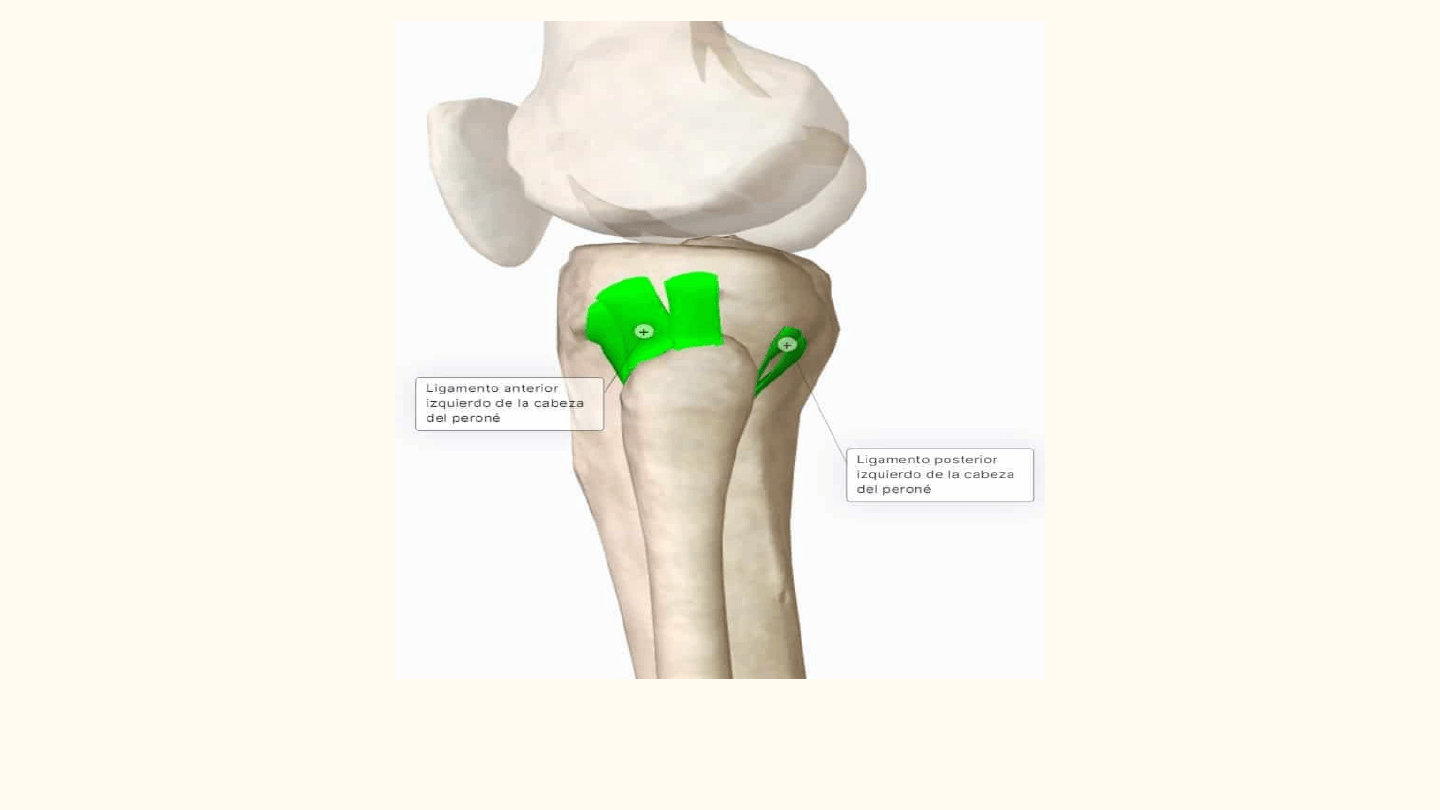

❖ Une la cabeza del peroné al extremo superior

de la tibia.

❖ SINOVIAL

❖ PLANA

❖ DOS SUPERFICIES ARTICULARES

(condilo lateral de la tibia y cabeza del peroné)

❖ MEMBRANA SINOVIAL

❖ UNIÓN:

-UNA CÁPSULA ARTICULAR

FIBROSA

- DOS LIGAMENTOS (Ligamentos de

la cabeza del peroné, un anterior y un

posterior)

❖ Sólo puede ejecutar MOVIMIENTOS de

deslizamiento de escasa extensión.

Ligamentos posterior y anterior